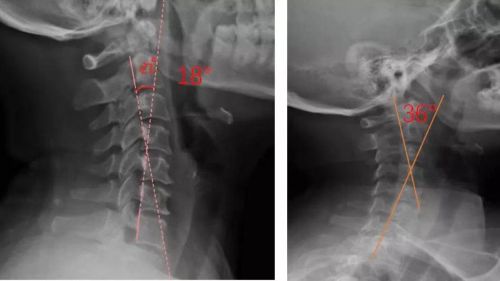

我們通過(guò)對(duì)頸部進(jìn)行光學(xué)掃描與頸椎側(cè)位X光檢查,測(cè)量頸椎曲度,由專業(yè)矯形器師結(jié)合患者的情況設(shè)計(jì)個(gè)性化頸椎枕,部分或全部3D打印工藝制作完成,矯正頸椎的生理曲度。患者適配后拍攝X光片,做到精準(zhǔn)矯正與治療,避免使用不適和矯枉過(guò)正。

患者適配前后側(cè)位X光,佩戴前18°,適配后36°

對(duì)于頸椎病患者,合理設(shè)計(jì)的頸椎枕,能夠緊密適合頸椎,矯正頸椎生理曲度;再根據(jù)頸椎曲度改善情況,隨時(shí)間慢慢調(diào)整3D打印頸椎枕曲度,使變直的頸椎逐漸形成正常的生理曲度,改善頸肩痛的癥狀。